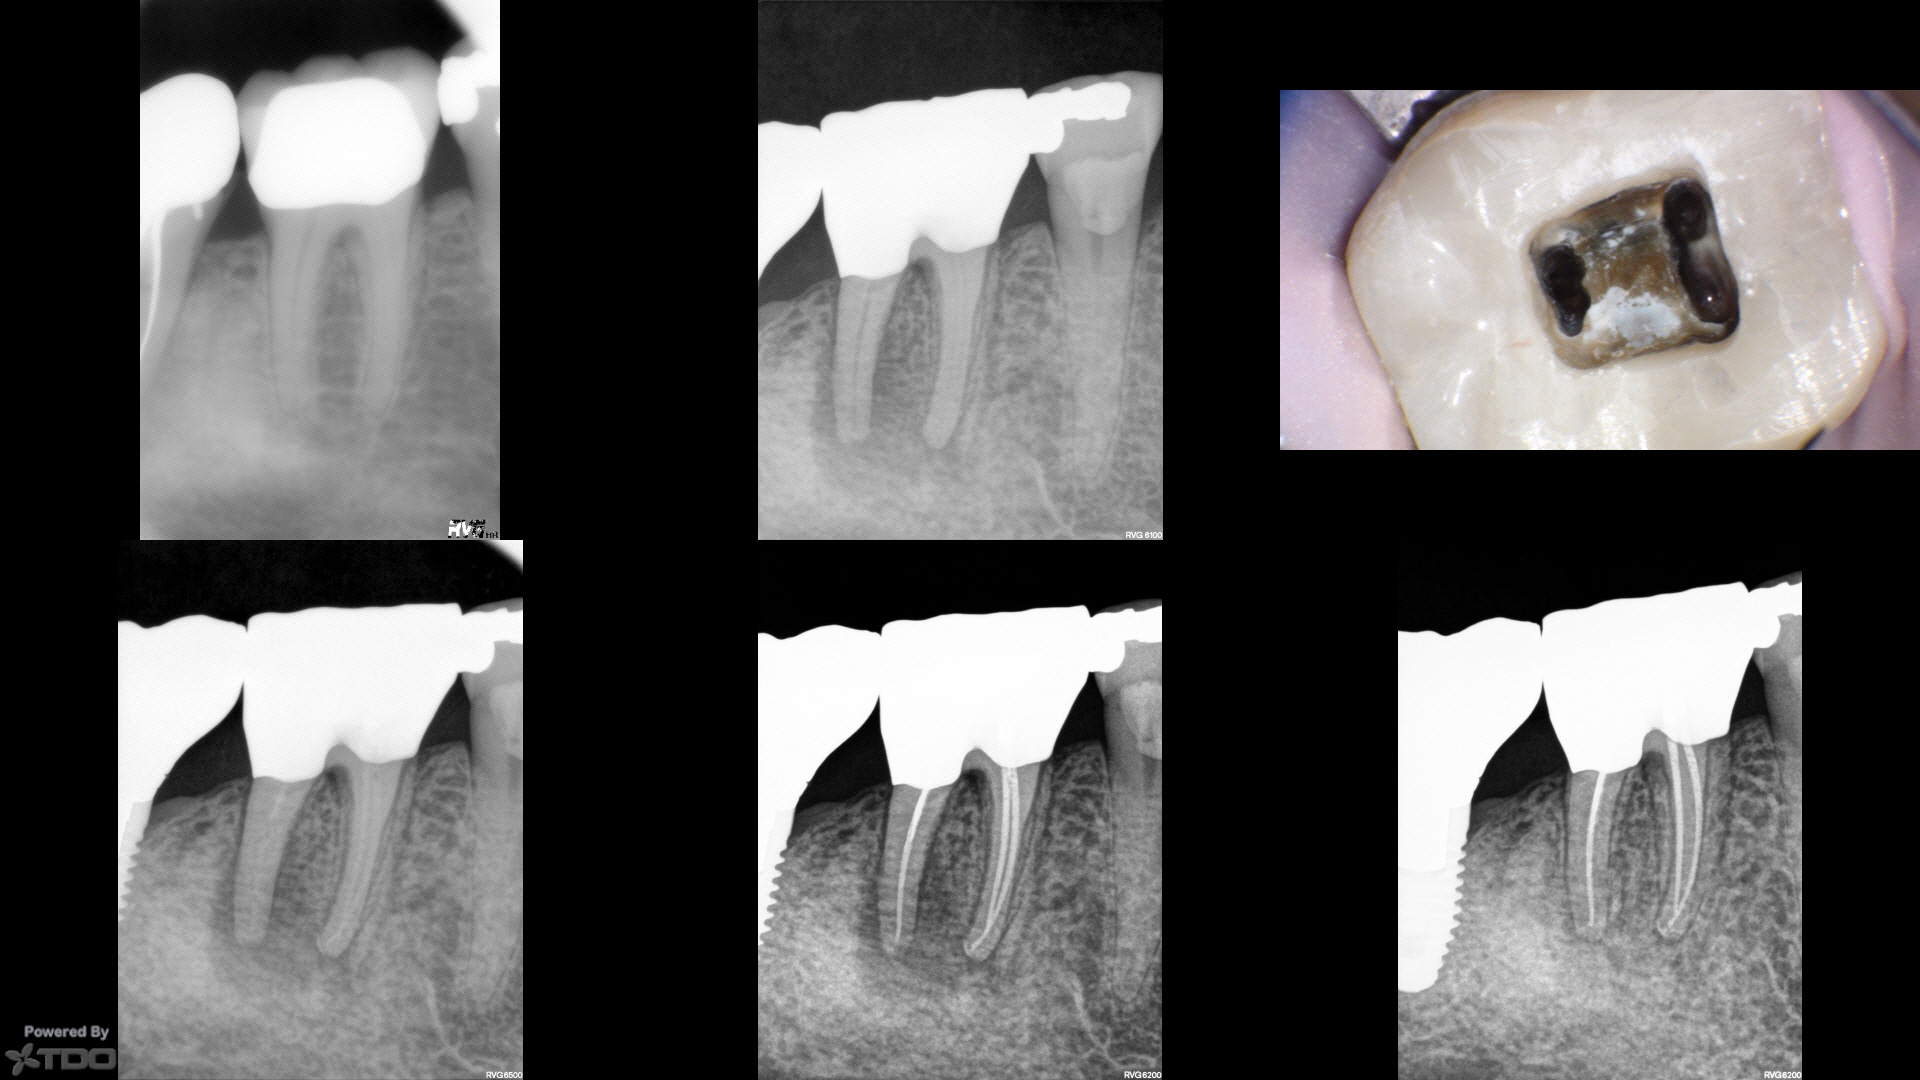

I took a look at it and knew there wasn't going to be any point in a traditional access…i.e. even if I cut a traditional access, it would be a search and try-not-to-destroy in the roots.  Found four PONs. CBCT in CH to check (not shown).

So instead, I cut a wide swath through the Zirc (stepped access) and accessed each root individually…aka "dual" or "truss" access.

Pure SSW 17/V.04 shapes in all four PONs.

Amalgam crown repair.